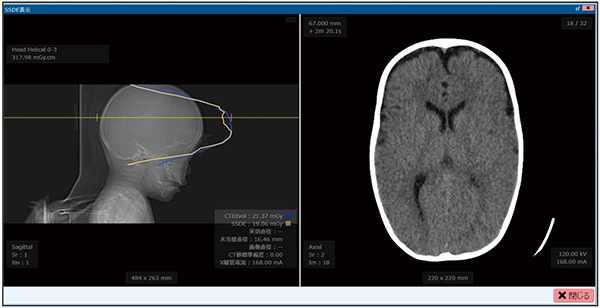

ARIStation iSEDでは,アキシャル画像の画素サイズと画素値を用いて水等価直径を求め,精度良くSSDEを算出する方法を採用している。2019年7月に公開されたAAPM Task Group 293: Size-Specific Dose Estimate(SSDE)for Head CTにいち早く対応し,SSDEをスライス位置ごとに算出が行える(図1,2)。

図1 小児頭部SSDE解析表示

(青色:CTDIvol,黄色:SSDE)

位置決め画像上でカーソルを移動させることで,任意のスライス位置でのSSDE値を表示可能。